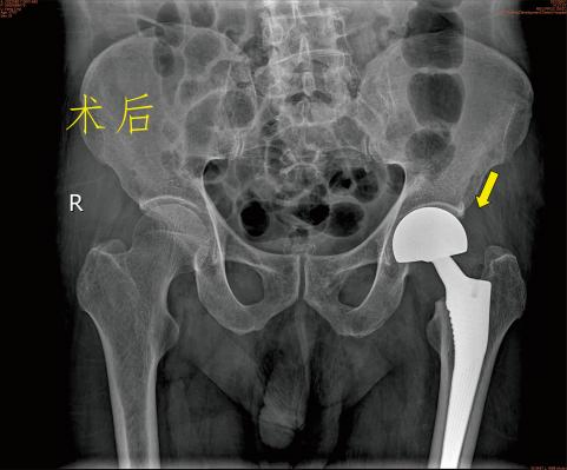

保守治疗 一般说的是卧床、牵引固定,等待骨折自己愈合。费用看似低廉,不用开刀出血,感觉上好像很安全,但老年人由于年纪大、体质差、新陈代谢水平低等原因,发生骨折后的愈合时间较长,所以保守治疗的缺点更多: 2.卧床时间长:髋部由于位置特殊,不像上肢骨折一样可以夹板石膏固定而不影响日常活动,一般髋部骨折通常要床边牵引制动2~3个月甚至更长,吃喝拉撒都在床上。看似很安稳,其实对于患者来说很痛苦。 3.并发症多:长期卧床容易产生褥疮;坠积性肺炎。泌尿系感染、深静脉血栓形成等,严重者危及生命。 4.治疗效果欠佳:单纯的牵引治疗很难保证复位质量。多数患者的骨折容易畸形愈合甚至不愈合,下肢短缩跛行,影响以后的生活质量。 5.加重骨质疏松:长期卧床、制动、骨量大量丢失,使原本的骨质疏松更加雪上加霜。 手术治疗 股骨颈骨折根据骨折移位情况,患者身体状况、年龄、预期寿命等因素,选择空心钉内固定术、人工半髋关节置换术或全髋关节置换术。股骨粗隆间骨折,一般采用闭合复位防旋髓内针内固定术或人工髋关节置换术。股骨粗隆下骨折主要是切开复位髓内针内固定术,很少使用钢板内固定术。 虽然老年髋部骨折术后死亡率高,国内外对其治疗方式争论不断,但研究表明。手术在降低死亡率、并发症发生率方面有明显优势。选择合适手术方式治疗老年髋部骨折可有效的降低死亡率、并发症发生率、改善患者生存质量。真正提高他们的生活质量。 更有多个研究发现,老年髋关节周围骨折的病人采取保守治疗之后的一年内死亡率接近50%!长期卧床引起的并发症,不管是褥疮、血栓、坠积性肺炎还是各种感染,都有可能会是致命的,这才是导致患者死亡的根本原因。 对此我们建议:在符合手术指征的前提下,老年髋部骨折应优选手术治疗。 九江市第一人民医院开发区分院/朱挺平